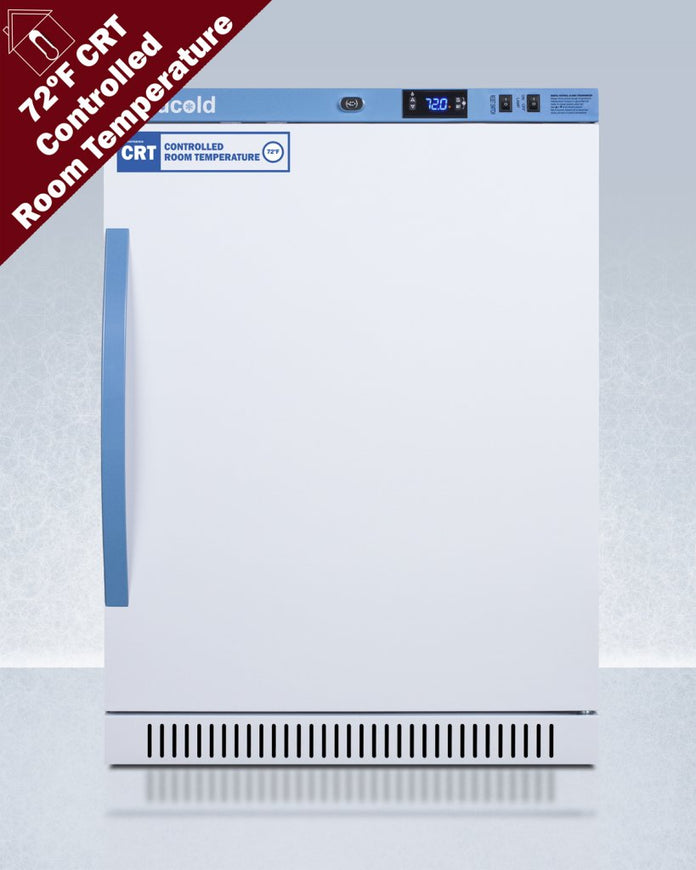

Accucold - ARS6PV-CRT - 6 Cu. Ft. ADA Height Upright Controlled Room Temperature Cabinet

Accucold's Performance Series Controlled Room Temperature Cabinets offer purpose-built storage solutions for medication requiring a stable room temperature environment.

The ARS6PV-CRT is a 6 cu.ft. upright unit pre-set to 72ºF, with an adjustable range from 68º to 77ºF. It is sized at 32.5 inches high for use in most ADA compliant applications. The microprocessor temperature controller is externally located to minimize door openings, helping to protect stored contents from ambient temperature. The buffered temperature probe is encased in a glycol-filled bottle to better simulate temperature of the stored product, with an additional sensor that reads air temperature to ensure superior temperature control. The current and min/max temperature display is viewable in Celsius or Fahrenheit to the nearest tenth of a degree. The audible and visual temperature alarm sounds if the unit's interior goes out of range. Additional alarms include a power failure alert, door open alarm, and sensor failure alarm. This unit is equipped with remote alarm contacts in the rear and a 1/2" probe port on the right side to accept additional monitoring devices. A hospital grade cord with 'green dot' plug is also included for added safety in high traffic areas.

The ARS6PV-CRT comes in a white cabinet finish with a blue accented control panel. The factory-installed antimicrobial handle is powder-coated with naturally occurring silver ions, which help to reduce the spread of germs, allowing for a safer, cleaner user experience. The user-reversible door ships with a right hand swing and self-closing function (note: self-closing is disabled once reversed to LHD). This model includes a factory-installed lock and ships with two keys for staff use. Powerful magnetic gaskets ensure a positive seal.

Designed with hydrocarbon refrigerant, the ARS6PV-CRT provides an energy efficient solution to stabilized room temperature storage, even when ambient temperatures can reach temperatures as cold as 68ºF or warm as 86ºF. This unit is Pyxis, Omnicell, and AcuDose RX compatible. Additional sizes, as well as glass door options, are also available.